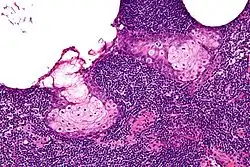

| High magnification micrograph of a sebaceous lymphadenoma. H&E stain. | |

Sebaceous lymphadenoma is a benign tumour of the salivary gland.[1]

Sebaceous lymphadenoma is a tissue diagnosis, e.g. salivary gland biopsy.

It may be confused with a number of benign and malignant neoplasms, including Warthin tumour, mucoepidermoid carcinoma and sebaceous lymphadenocarcinoma.[2]